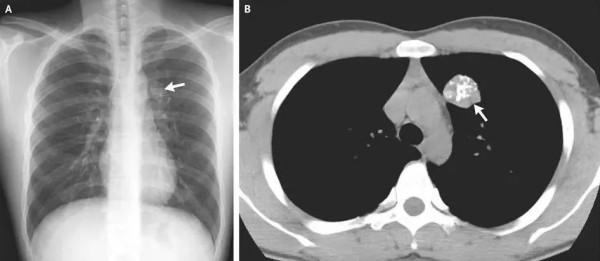

事实上,在X线片、CT、钼靶、超声报告中,常常会出现“钙化”“钙化灶”的字样。钙化,指人体内的钙离子以磷酸盐或碳酸盐形式,发生沉积的过程。很多钙化是在人体病变修复过程中形成的,整个过程和伤口愈合结疤类似。通常表现为钙盐沉积在受损组织中,使这些组织变得坚硬。

人体绝大部分组织和器官内都可能出现钙化,比如头颅的脑膜、基底节区,胸部的肺、肋软骨、胸骨剑突,腹部的肝脏、肾脏,以及甲状腺、乳腺和前列腺等腺体,还有遍布身体的大多数动脉和静脉血管。钙化存在的广泛性也使得它成为体检和平时检查中影像学报告上的“常客”。